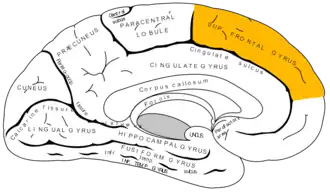

Medial surface of left cerebral hemisphere

Medial surface of left cerebral hemisphere -